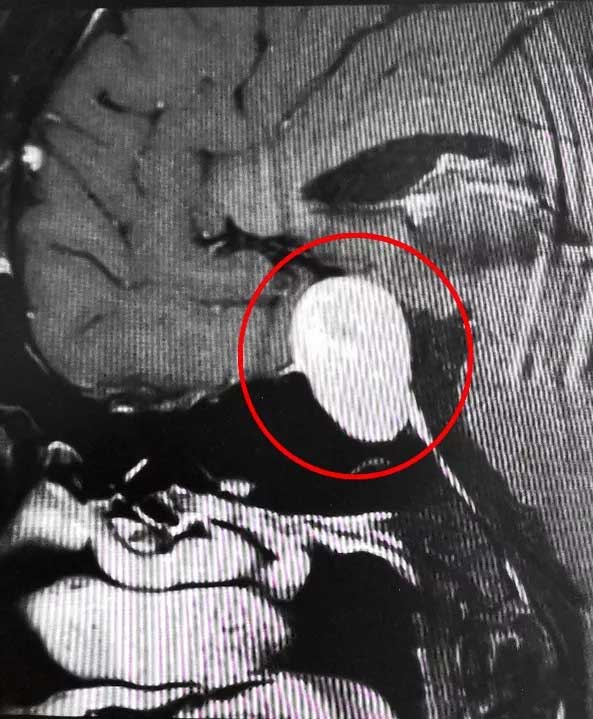

近期,上海藍十字腦科醫(yī)院6B病區(qū)收治了這樣一位典型患者。一位男性垂體瘤患者,患者一年前出現視物模糊情況,起初他以為是眼睛問題,但是到醫(yī)院眼科檢查時未查出明顯異常。來院后經檢查,患者雙側視野缺損,后經醫(yī)院MR檢查確診為3公分垂體巨大腺瘤;颊呤中g指征明確,無明顯手術禁忌,在征得家屬同意后,李士其教授在吳治群博士協助下經蝶竇入路成功為患者進行了手術,顯微鏡下將鞍內腫物切除。經過十余天恢復,目前患者已順利出院。

▲ 垂體巨大腺瘤超蝶鞍生長